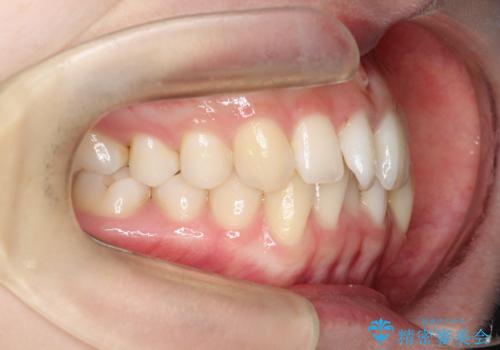

【インビザライン】 前歯の反対咬合を治したい

左下5番は先天性欠損のため乳歯は抜歯しインプラントにて欠損補綴しています。